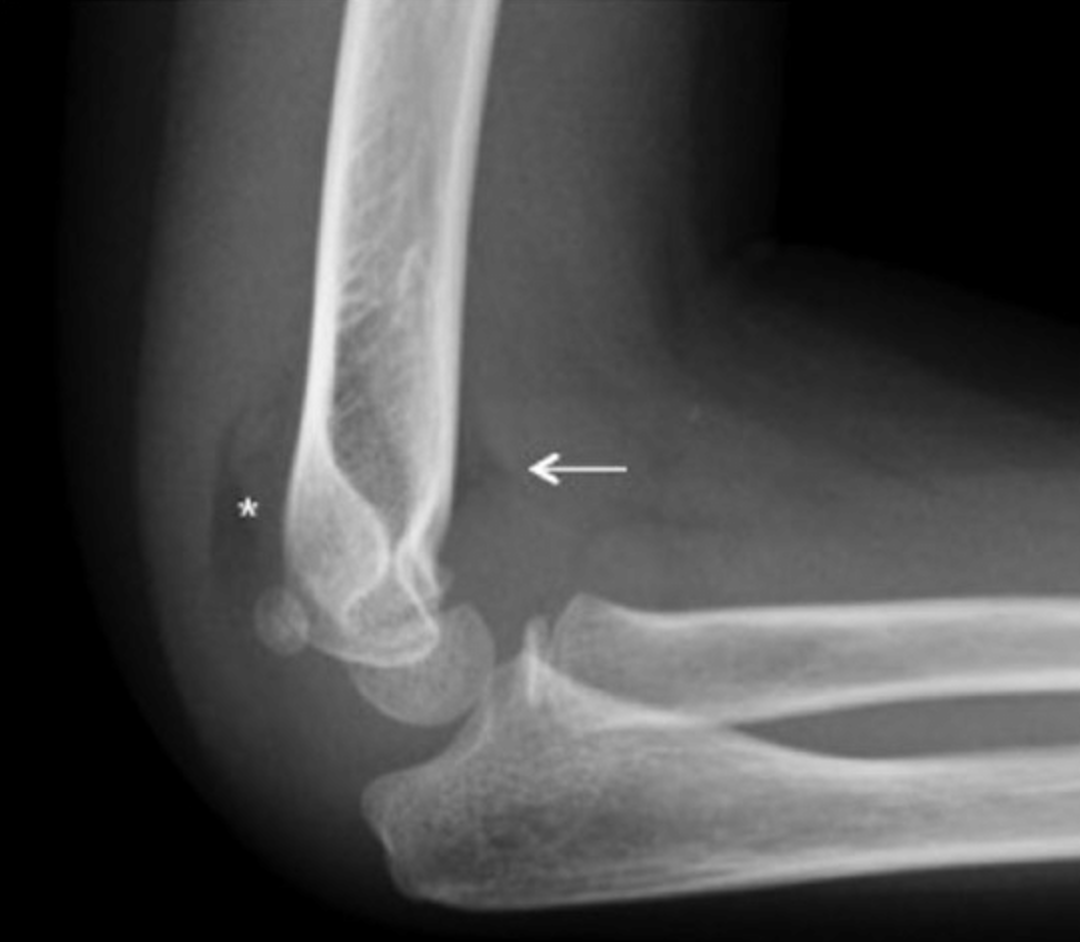

Fat-pad-sign = indirektes Frakturzeichen